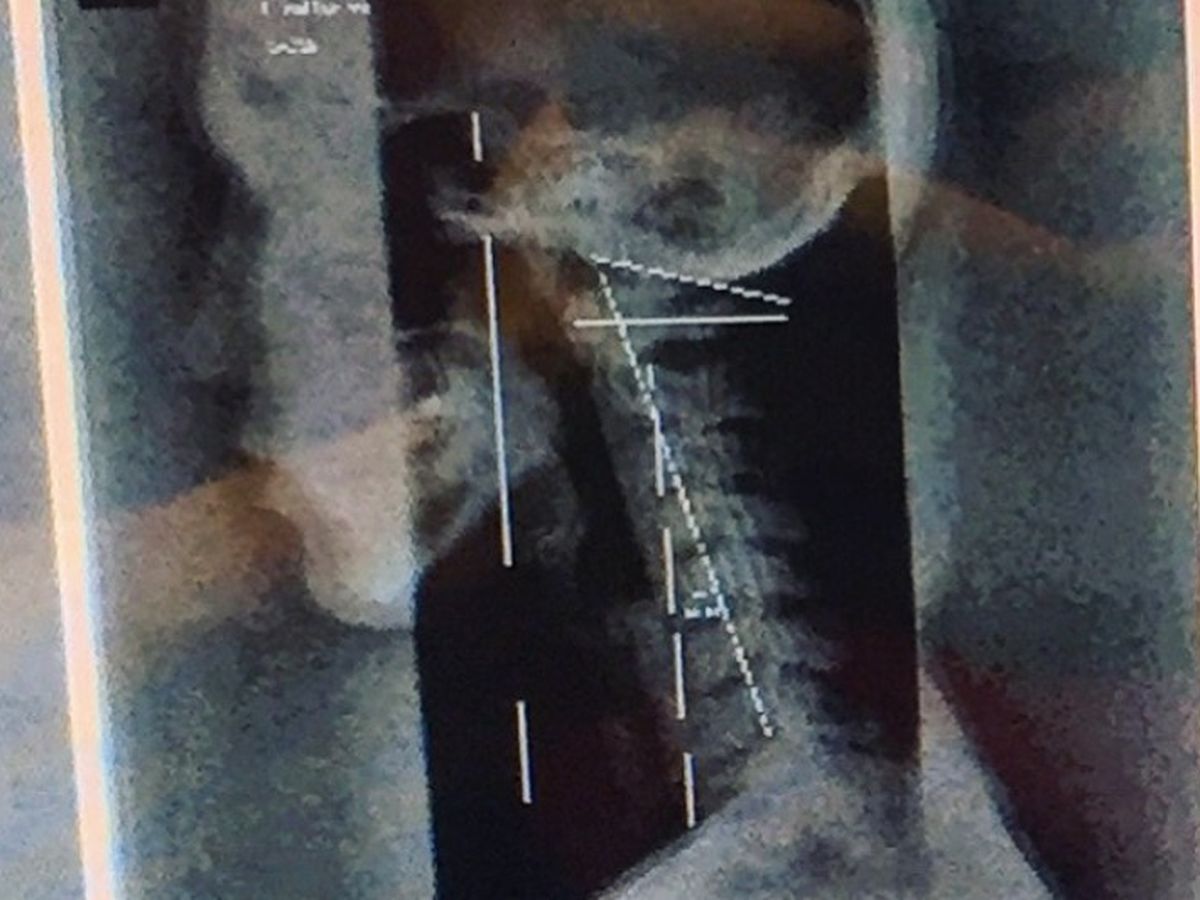

Within the past two months I have since learned, via x-ray, that my neck itself is actually sitting pretty at negative fourteen degrees. This has been putting pressure on a good amount of my nerves that usually sweep under the base of the skull and reaches like vines down the spine and out to my innards. Within two weeks of learning about my neck, I ended up fainting in the shower, smacking my head, and getting a concussion.